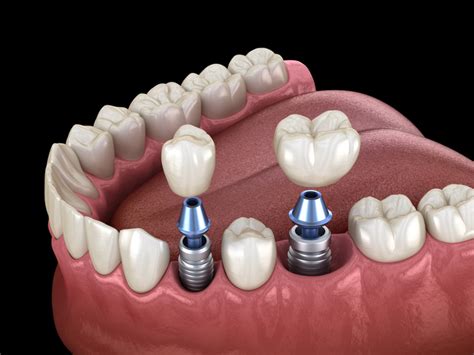

Las razones médicas para la extracción de las muelas del juicio son variadas y significativas. Principalmente, el problema surge cuando no hay suficiente espacio en la mandíbula para acomodar estos molares, lo que puede llevar a que crezcan de manera impactada o torcida.

Sobre el momento óptimo para la extracción, se recomienda generalmente durante la adolescencia tardía o al inicio de la veintena.